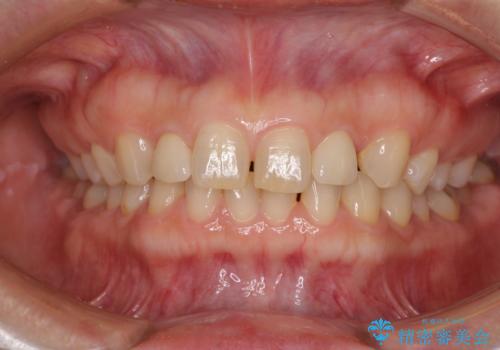

前歯の隙間や、周りの歯と色合いの違いなどはあまり気にしていらっしゃらなかったため、矮小歯の2歯を自然な大きさに仕上げました。

とても自然な歯が装着されたとのことで、患者様には大変満足していただきました。